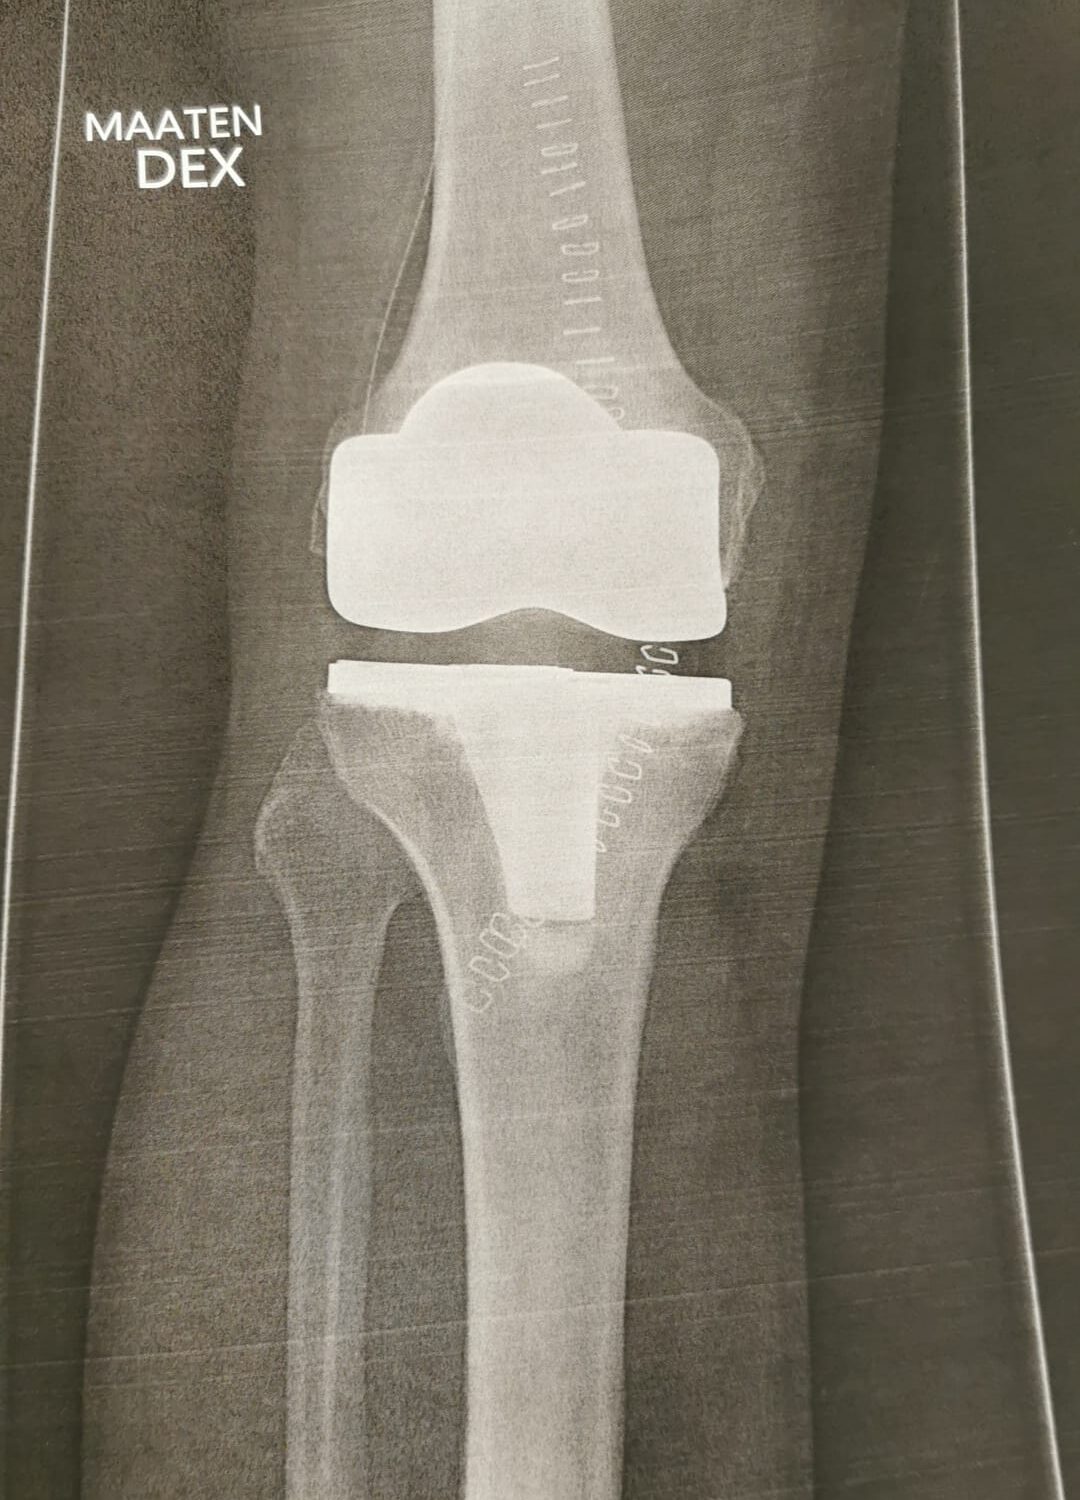

Viikolla 6 vuorossa oli jälkitarkistus ja tapaaminen Ortonissa, jossa käytiin läpi vielä aikaisempaa tarkemmin leikkaus ja sen kriittiset vaiheet. Pääsin myös samalla esittämään monia ortopedisiä kysymyksiä, jotka olivat mieltäni askarruttaneet. Polveni oli ollut normaalia haastavampi leikattava aikaisemman polvivammani vuoksi.

Polvi oli odotettua isompi työmaa kirurgille

Palaan vielä hetkeksi omaan tapaukseeni, koska lähtökohtani leikkaukseen ei ollut se perinteinen. Seuraava teksti on tarkoitettu ensi sijaisesti fysioterapeuteille ja muille alan ammattilaisille, mutta toki muutkin saavat siitä taustatietoa.

Kun sain leikkauskertomuksen luettavakseni sairaalassa, minun piti lukea se muutamaan kertaan läpi ennenkuin ymmärsin, että kaikki ei mennytkään niin kuin normaalissa leikkauksessa, jossa potilaalla ei ole aikaisempaa vammahistoriaa. Sen kyllä tiesin, että polven alueella on arpikudosta, mutta lähtötilanteenki oli paljon huonompi kuin odotin.

Avaus siis tehtiin vanhaan arpeen joka oli muodostunut kolmen leikkauksen seurauksena. Sen iho on hyvin ohut ja vanhan avauksen kohdalla erittäin tiukasti faskiatasoon arpeutunut. Avauksen tekeminen vei rutkasti aikaa, mutta ihon ja faskian irrotus lopulta onnistui taitavalta kirurgilta!

Polvinivelessä oli runsaasti osteofyyttejä eli luupiikkejä ja polvilumpio oli tiukka eikä sitä saatu käännettyä. Paljastui myös että aikanaan korjattu etummainen nivelside oli toimimaton ja kutistunut olemattomaksi.

Sääriluun yläpinta oli lasimainen ja kun siihen sovitettiin tekonivelen komponenttia, luuhun kiinnitetty metallihakanen piti ensin saada ulos. Se vaati kohtalaista vaivannäköä ja talttaamista. Lisäksi sääriluun vinoutunut asento piti vielä korjata sahaamalla. Kun se oli tehty, komponentit asetettiin paikalleen, haava suljettiin ja haava suljettiin metallihakasilla. Onneksi olin unessa kaiken tämän aikana.

Kaikki edellä kerrottu tarkoittaa, että joudun kiinnittämään tavallista enemmän huomiota arven elastisuuteen. Todennäköisesti polvilumpion alaosaan jää joustamatonta ihoa, mikä näkyy hyvin myös videoissa. Ei tästä ihan täydellistä tule mutta toimiva kyllä. Vastuu on minun, ei muiden.